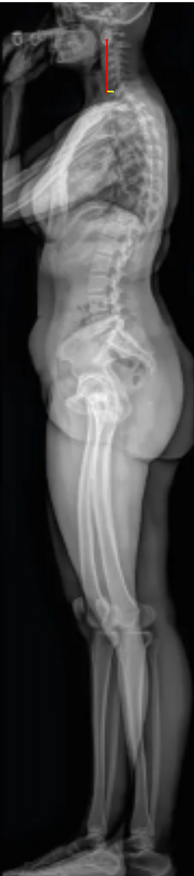

The C2–C7 Sagittal Vertical Axis (cSVA) quantifies the sagittal alignment of the cervical spine and represents the horizontal distance between the C2 plumb line and the C7 vertebral body on a standing lateral full-spine X-ray.

It provides insight into cervical sagittal balance and how the cervical spine contributes to overall sagittal alignment.

An increased cSVA indicates anterior translation of the head relative to the cervical spine, reflecting positive sagittal malalignment, often associated with forward head posture, cervical deformity, or compensatory changes to maintain horizontal gaze.

• Drop a vertical plumb line (parallel to the gravitational vertical) from the C2 centroid.

• Measure the horizontal distance (in millimeters) between this vertical line and the posterior–superior corner of C7.

• If the C2 plumb line lies anterior to C7, record as a positive cSVA (forward head posture).